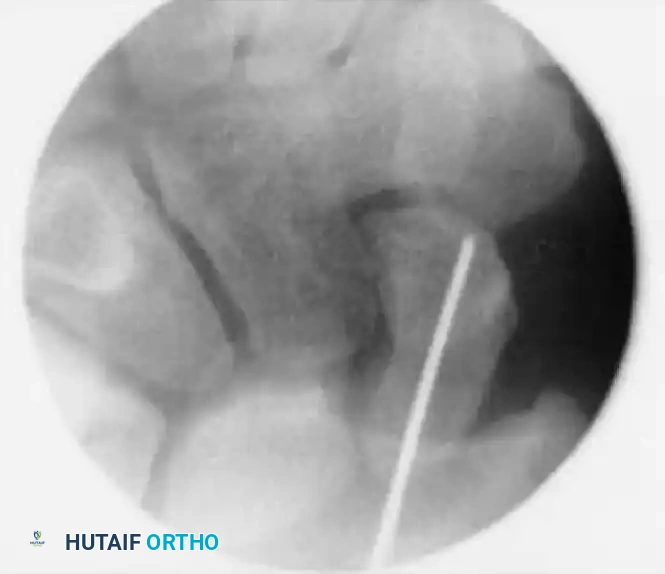

2. Incision and Guidewire Insertion

• Make a small (3-5 mm) skin incision at the marked location. Use a hemostat for blunt dissection down to the dorsal capsule of the wrist joint to protect the extensor tendons and terminal branches of the superficial radial nerve.

• Load a double-pointed 0.045-inch (1.14-mm) K-wire into a powered wire driver.

• Insertion: Under live fluoroscopic control, insert the wire starting at the exact center of the proximal pole (the center of the "ring").

• Pass the guidewire from dorsal to volar, directing it down the central axis of the scaphoid and out through the trapezium.

• Technical Tip: Use a 12-gauge angiocatheter over the K-wire to protect the dorsal soft tissues during insertion. Keep the wrist flexed during this step to prevent the guidewire from bending against the radius.

Guidewire Insertion A

Guidewire Insertion B

Guidewire Insertion C

FIGURE: (A, B) The guidewire is placed at the base of the proximal pole and driven along the central axis. (C) The wrist is extended, and fracture alignment alongside guidewire position is confirmed.

• Advance the wire through the distal pole and out the palmar surface of the hand.

• Reverse the wire driver and pull the wire distally just enough so that the dorsal (trailing) end clears the radiocarpal joint. This allows the wrist to be fully extended.

• Extend the wrist and use the C-arm to confirm scaphoid fracture alignment and the central positioning of the guidewire in all planes.